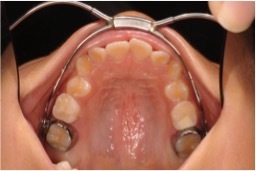

上あごの歯列が前にずれて咬み合っている患者さんに使用し、上あごの6歳臼歯を後ろに移動させます。小学3,4年生頃から開始することが多いです。それよりも早くに開始する必要はありませんが、6歳臼歯の後ろに12歳臼歯が生えてくると効果がでません。少し余裕を持って3,4年生頃から開始します。

下図のように、上あごの6歳臼歯に取り付けた金具とフェースボウ、ネックバンドの3つのパーツから構成されています。

上あごの6歳臼歯に金具を取り付けます。

これは固定式で取り外しはできません。

上あごの6歳臼歯に取り付けた金具に装着する器具です。フェースボウといいます。取り外し式です。

上あご6歳臼歯の金具にフェースボウを取り付けたところです。就寝時のみ使用します。